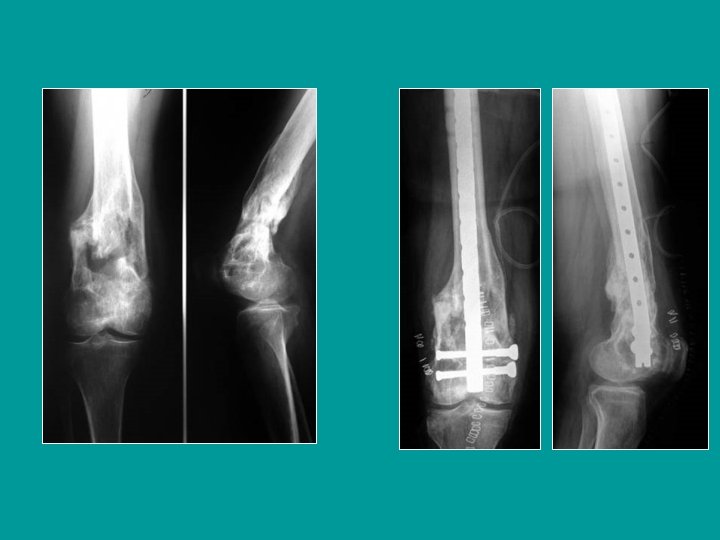

Fractura supra e inter-condílea Fractura articular conminutiva

Fracturas conminutivas Clavo-placa AO Placas en puente sobre la conminución

Clavo endomedular retrógrado Introducción desde la rodilla (por debajo de la tróclea) estabilización con tornillos en las 2 extremidades